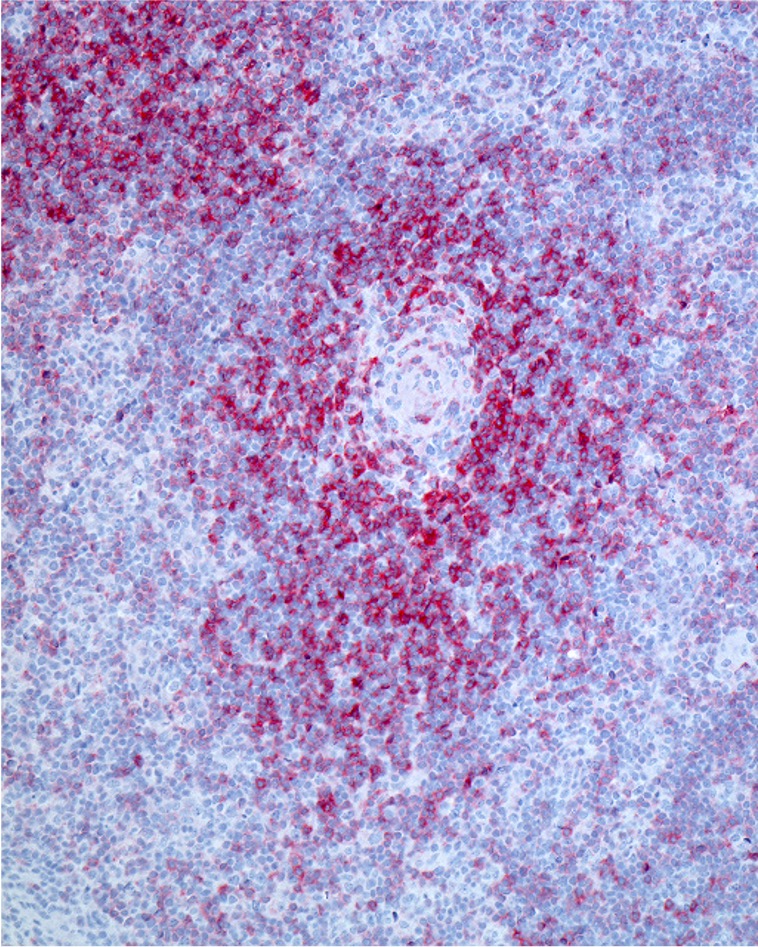

Ziel des Projekts ist, die Heilungschancen von Betroffenen deutlich zu erhöhen. Die Beteiligen möchten durch den smarteren und zielgenaueren Einsatz bekannter Therapien die Behandlung von T-Zell-Non-Hodgkin-Lymphomen verbessern, einer oft aggressiven Form von Lymphdrüsenkrebs. Solche T-Zell-Lymphome entstehen aus fehlgesteuerten Abwehrzellen des Immunsystems.

„REACT hat das Potenzial, einen neuen Behandlungsstandard für T-Zell-Lymphome zu definieren“, sagt Prof. Dr. Andreas Hüttmann, Leitender Oberarzt der Klinik für Hämatologie und Stammzelltransplantation am Universitätsklinikum Essen. Entscheidend sei die enge Zusammenarbeit von Kliniker:innen, Nuklearmediziner:innen, Statistiker:innen und Studienzentren. 20 Unikliniken wirken als Prüfzentren mit. „Nur diese gebündelte Expertise hat die Förderung möglich gemacht, und sie eröffnet neue Perspektiven für schwer erkrankte Menschen.“ Neben ihm und seinem Essener Team ist die Universitätsmedizin Göttingen mit Prof. Dr. Gerald Wulf gleichberechtigt beteiligt an dem REACT-Projekt mit dem Titel „Allogene Zell-Therapie bei refraktären T-Zell-Lymphomen“. ACT steht für Allogeneic Cell Therapy und RE beschreibt das Reagieren auf einen PET-Befund.